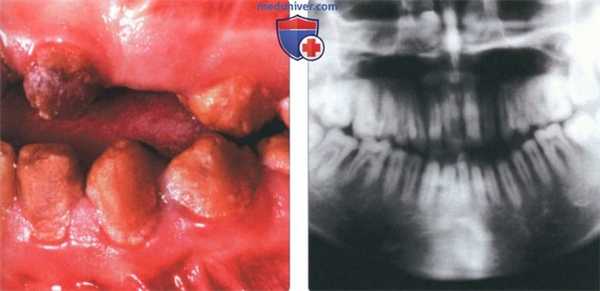

(Слева) На фотографии видна тонкая шероховатая поверхность остатков эмали коричневого цвета у пациента с гипоминерализационным несовершенным амелогенезом. Обратите внимание на передний открытый прикус.

(Справа) На кадрированной панорамной рентгенограмме визуализируется эмаль такой же рентгеновской плотности, как и подлежащий дентин, что характерно для гипоминерализационного и гипоматурационного типов. Зубы выглядят заостренными, проксимальные контакты отсутствуют.